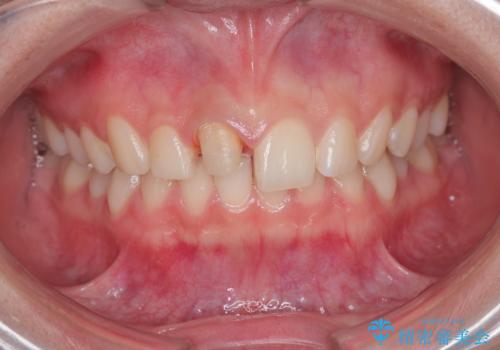

- 前歯が欠けたとの事で来院。

セラミックを希望されたので根管治療からやり直しました。

- ジルコニアクラウンスタンダード・仮歯 13.2万円 精密根管治療(リトリート)・ファイバーコア 12.1万円費用は治療当時の料金となります